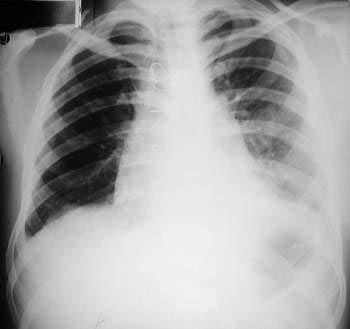

un paciente joven, con un gran tumor del mediastino anterosuperior de rápido

crecimiento, correlacionando su tamaño entre la radiografía

del tórax y los hallazgos tomográficos realizado 15 días

después, y las condiciones físicas al momento de su intervención,

con gran dificultad respiratoria.